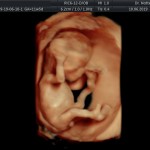

- De la edad gestacional (precisión en el cálculo del tiempo de embarazo).

- Crecimiento fetal.

- Las Estructuras Anatómicas Fetales, diagnóstico precoz de Malformaciones Severas importante mencionar que las malformaciones pequeñas y moderadas solo podrán ser detectadas entre la 18va a 22da semana de gestión (5to mes).